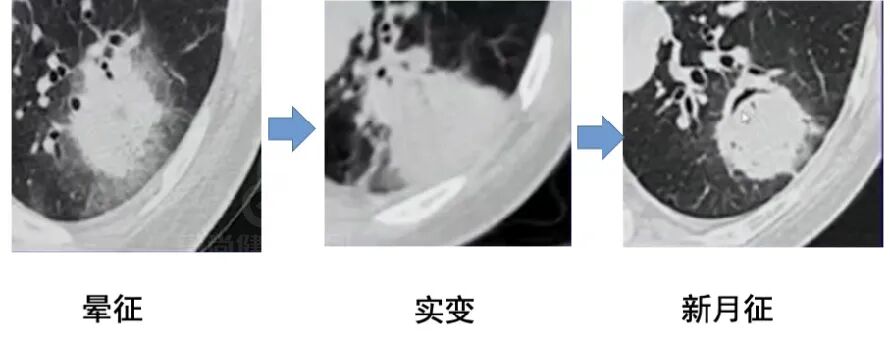

影像学表现——晕征样结节和楔形实变影

早期出现多发密度增高的结节影,周围可见晕征。「晕征」表现为围绕结节周围的略低于结节密度而又高于肺实质密度的环行带状区,其病理基础是肺曲菌破坏肺部小血管,导致肺实质出血性坏死。「晕征」是 IPA 早期最具提示性的特征性 CT 表现,也是活性曲霉菌存在的标志, 见于 40~69% 的早期病例,高峰期为病变的第 5 天(1-30 天)。

「楔形实变影「:表现为以胸膜面为基底节段性实变影,边缘模糊,与栓塞性肺梗死相似,病理基础为出血性肺梗死。

「空气新月征」:坏死空洞内部坏死组织回缩与空洞壁分离而形成。出现于病程后期中性粒细胞回升阶段。

晕征:凝固坏死+病变周围出血

早期影像表现:隐匿但关键

肺真菌感染(如侵袭性曲霉病、隐球菌病等)早期诊断困难,真菌侵袭早期,肺泡壁水肿或出血可表现为 GGO,传统认为空洞和空气新月征是肺真菌感染的典型标志,但研究发现,这些征象特异性虽高,却常在中性粒细胞恢复期或感染后 2-3 周才出现,相比之下,磨玻璃影(GGO)、微结节、树芽征(支气管簇集征)、(反)晕征出现更早,却因非特异性被忽视。